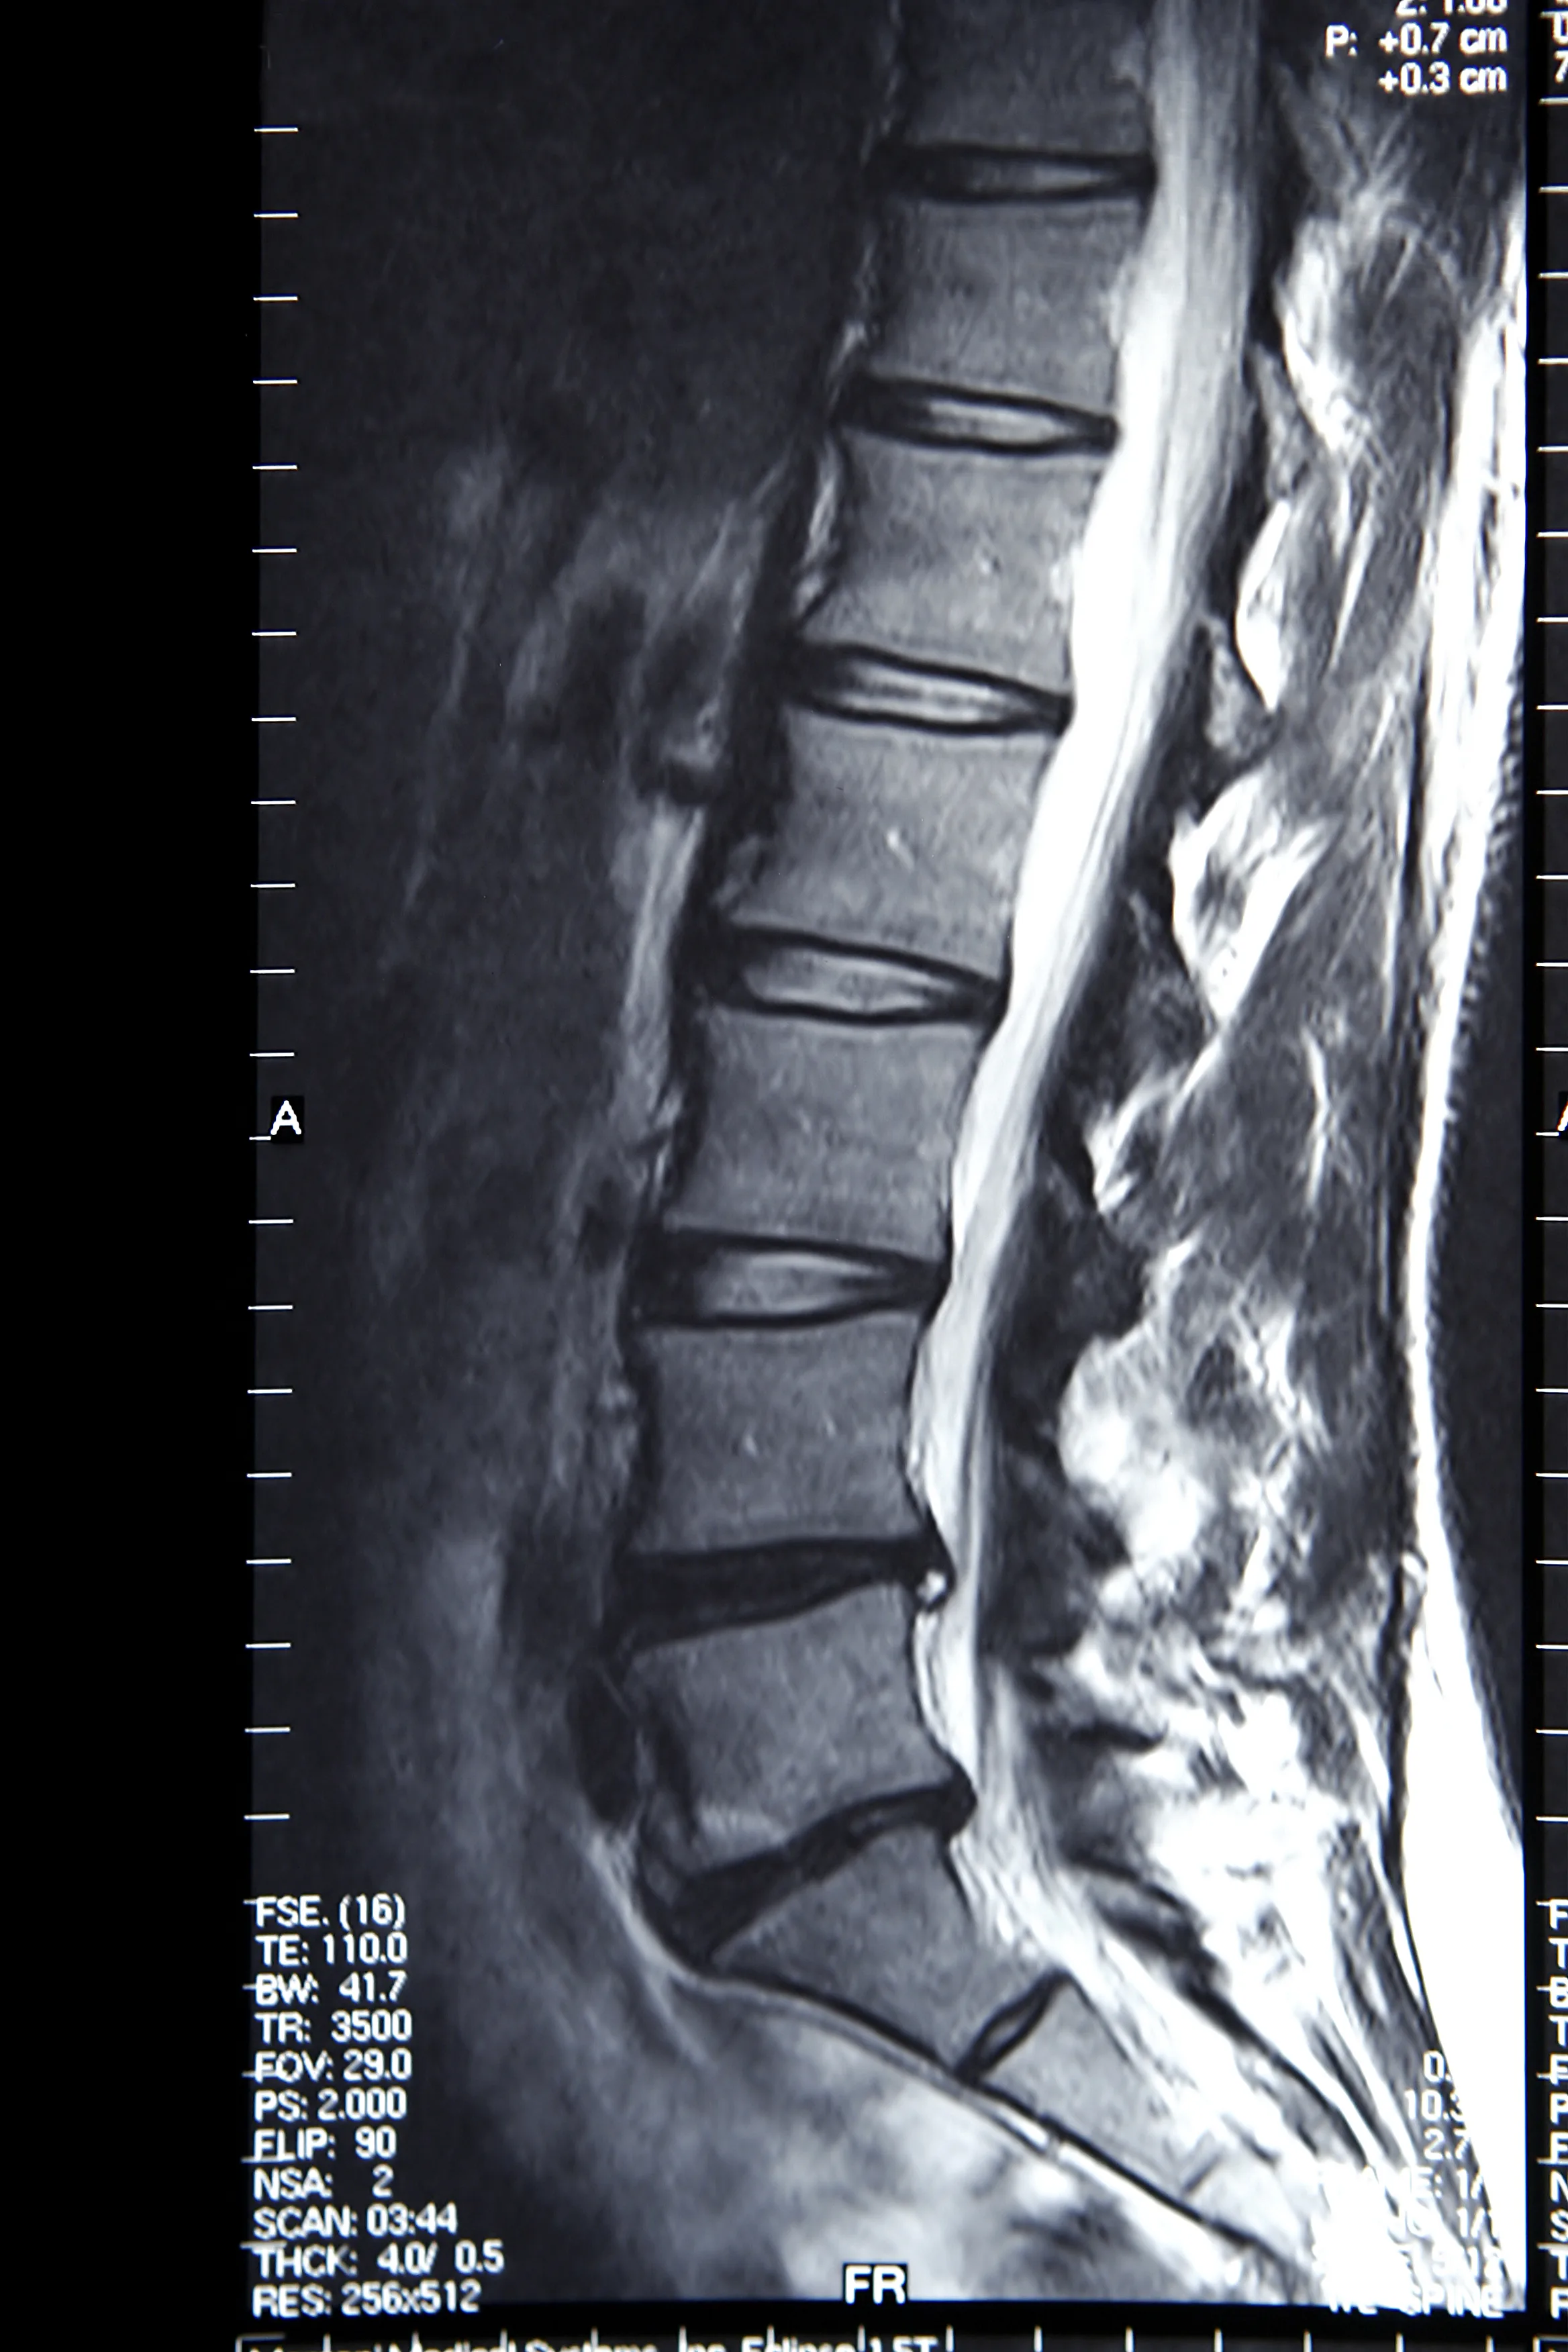

MRI of Spine Fusion Instrumentation

Individuals with spinal implants like screws or cages may have supervised MRI scans.

Patients who have had metallic devices surgically placed in their spine, such as pedicle screws or spinal interbody cages, may have an MRI scan under supervision, but the resolution of the scan is often severely obscured by the metal device and the quality of the imaging study is poor.

In general, stainless-steel implants cause more severe artifacts than titanium. Titanium is a paramagnetic material that is generally not affected by the magnetic field of MRI. For this reason, titanium has gained popularity for spine fusion instrumentation, and stainless steel has largely fallen out of favor due to the inability to get a clear postsurgical MRI scan.